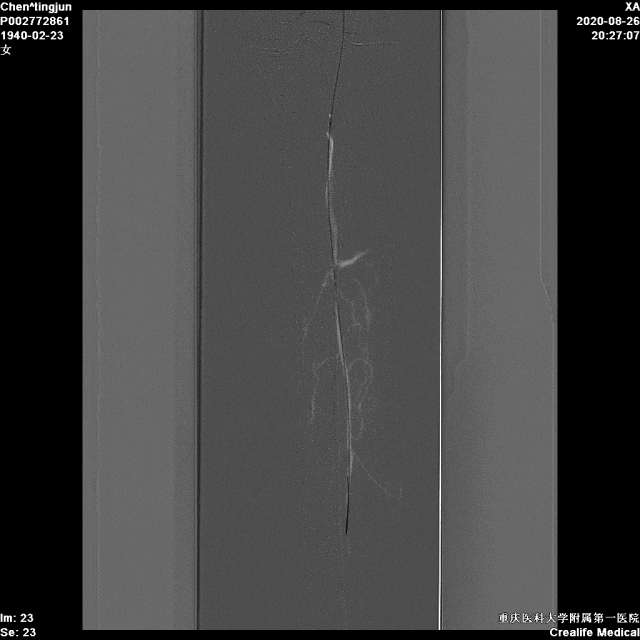

右股总-髂外闭塞,左股-腘动脉全程闭塞,膝下流出道显示不清,重度钙化

图:造影显示,股腘动脉全程闭塞,膝下流出道差